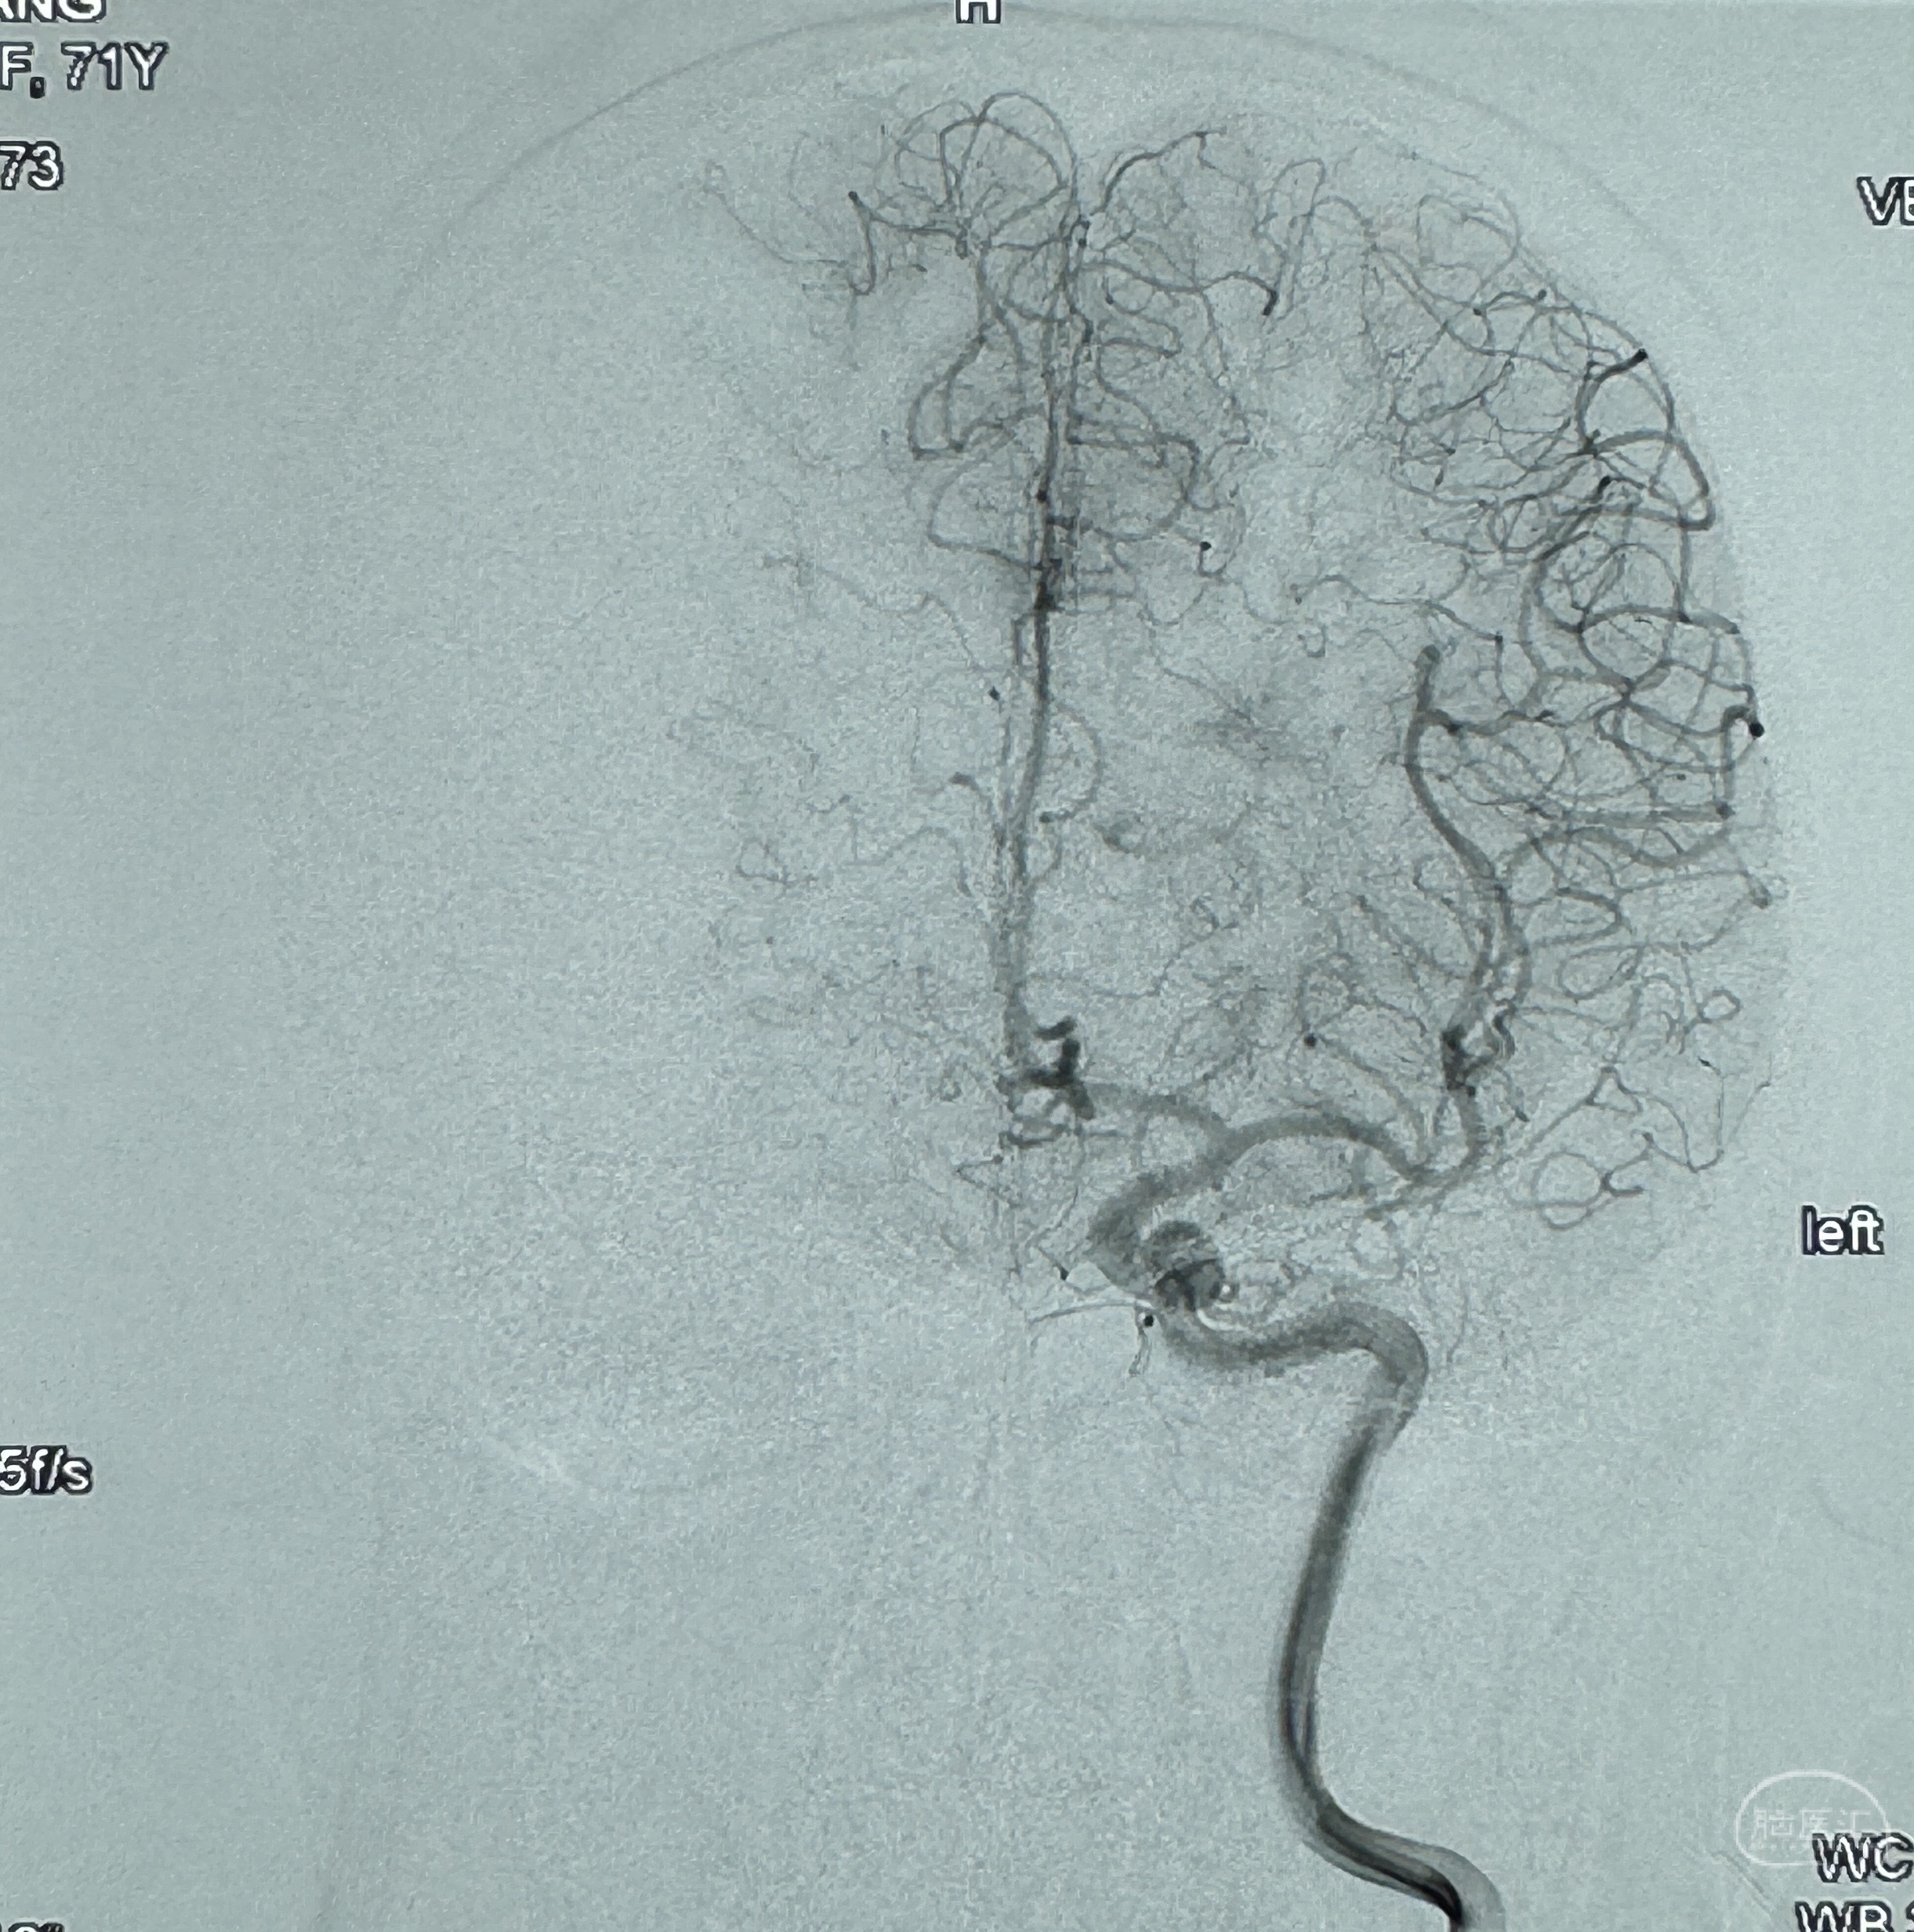

最后再看看颅内血管是否有异常

看动脉瘤内造影剂滞留,未见明确射流,遂撤出预留的栓塞微导管,快速结束手术,经导引导管灌注替罗非班250ug。

2023-12-27术后第十天复查DSA

支架贴壁佳,但可见射流,咋办?

支架植入顺利,贴壁佳,支架内血流通畅,动脉瘤内血液滞留明显